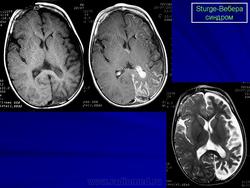

Магнитная резонансная томография пациента с болезнью Штурге - Вебера

Магнитная резонансная томография пациента с болезнью Штурге - Вебера